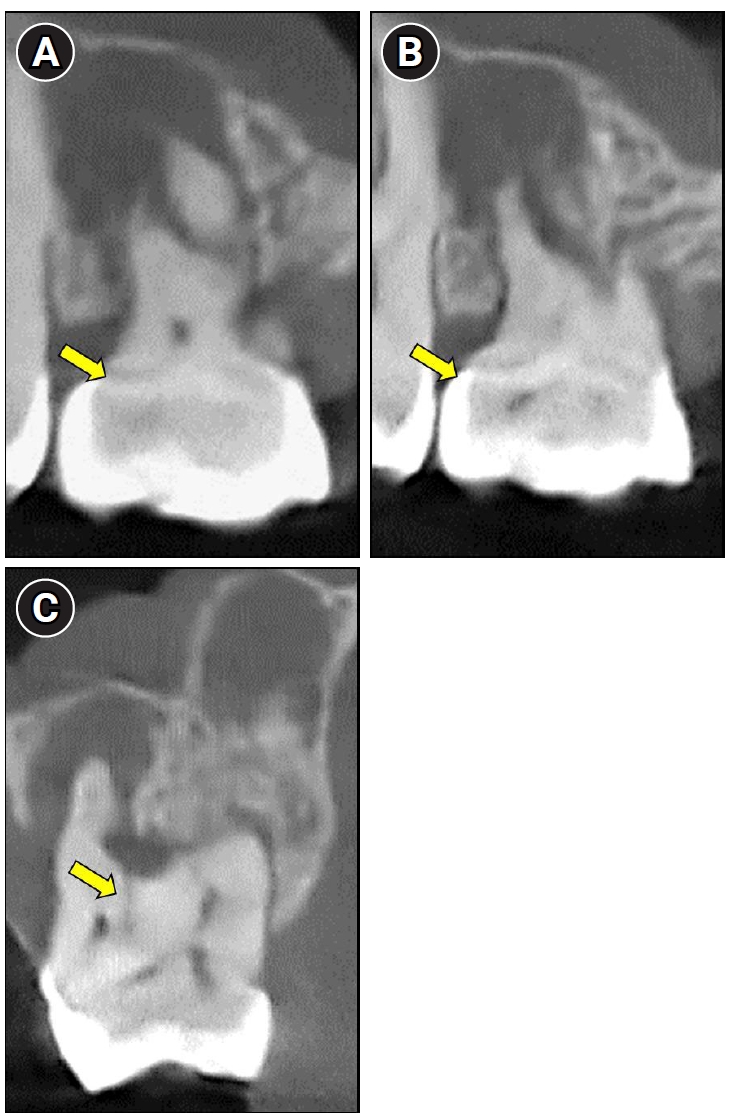

Cone-beam computed tomography images revealing characteristic anatomical features of molar-incisor malformation. (A, B) A dense mineralized structure consistent with a cervical mineralized diaphragm (yellow arrows). (C) An open channel (yellow arrow) connecting the furcation region to the pulp chamber.

In the present case, both a CMD and an open channel were identified, consistent with previously reported anatomical features of MIM (Figure 4A–C). A periapical lesion developed despite the absence of caries or visible fractures, which are typically associated with pulpal infection. This unusual clinical finding may be explained by the presence of structural anomalies commonly seen in MIM, specifically microporosities within the CMD and an open furcal channel. The CMD-associated microporosities could have acted as microchannels for bacterial ingress, promoting chronic intrapulpal infection. Additionally, the open channel observed in the furcation area may have established a direct connection between the oral environment and the pulp chamber, serving as a potential route for bacterial contamination. Together, these features likely contributed to pulpal pathology and the development of the periapical lesion in the absence of conventional etiological factors.